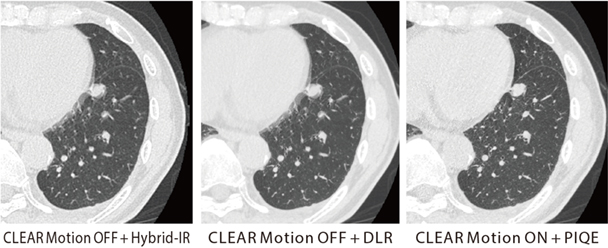

図2 原発性肺がん、肺転移症例で経過観察中

PIQE+ CLEAR Motionの併用で、心拍動に伴うアーチファクトを低減し、高い時間分解能かつ高精細画像の両立が期待できる。